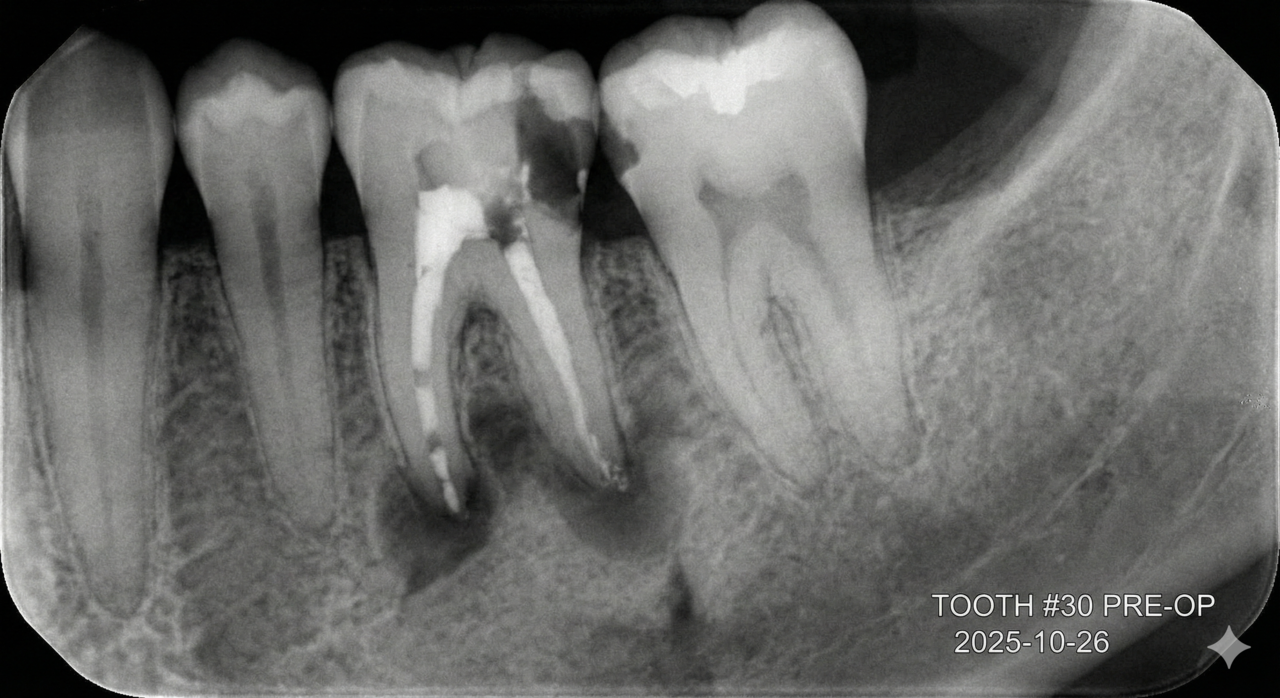

보이지 않는 신경관, 세균과의 싸움에서 타협은 없습니다.

신경치료의 본질은 '완벽한 감염 관리'입니다. 눈에 보이지 않는 치아 뿌리 끝까지 멸균 상태를 만들기 위해,

대학병원의 교과서적 원칙을 그대로 따릅니다.

재신경치료

다른 곳에서 포기한 치아, 디지털아트치과가 한 번 더 봅니다.

재신경치료는 과정이 까다롭고 성공률을 장담하기 어려워, 많은 곳에서 발치 후 임플란트를 권하곤 합니다. 하지만 우리는 압니다.

환자분에게는 '내 치아를 더 쓰고 싶은 간절함'이 있다는 것을.

정확한 실패 원인 분석 미세현미경을 통해 육안으로 보이지 않는 미세한 금(Crack)이나, 이전 치료에서 놓친 숨은 신경관을 찾아냅니다.

희망 고문 없는 정직한 진료 무조건 살린다고 장담하지 않습니다.

의학적 근거를 바탕으로 '살릴 수 있는 치아'와 '이제는 보내줘야 할 치아'를 정확히 판독하여, 환자분이 납득할 수 있는 최선의 길을 제시합니다.